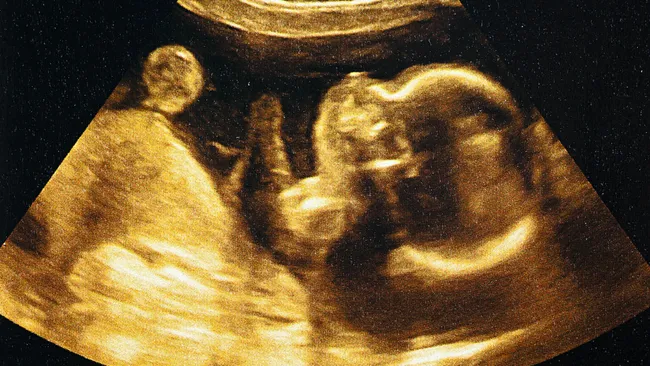

En este caso, la FDA otorgó un permiso especial para administrar el medicamento antes del nacimiento. A partir de la semana 32 de gestación, la madre comenzó a tomar risdiplam diariamente durante seis semanas. Esta estrategia buscaba que el medicamento llegara al feto a través de la placenta.